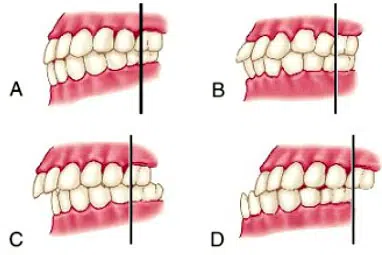

Mala oclusión dental. Relación entre los dientes y el dolor cervical

Se habla de una mala oclusión dental cuando hay una relación incorrecta entre el maxilar (arco superior) y la mandíbula (un arco más bajo), o un desalineamiento general de los dientes. Las malas oclusiones son muy comunes en la población. La imperfecta oclusión de los arcos dentarios puede ser causa de una desarmonía funcional o […]